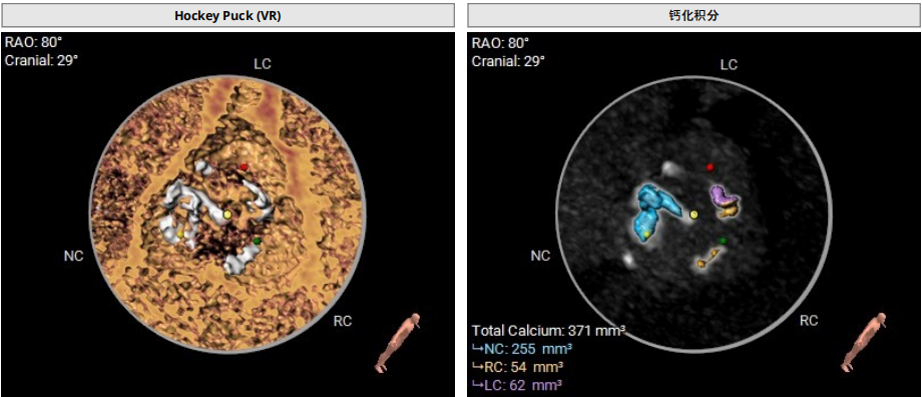

患者钙化情况

患者入路情况

• 患者为左右融合Type1型二叶瓣,左右窦瓣叶可见融合脊、钙化;

• 瓣环周长:81.3mm;

• LVOT周长:96.6mm

流出道结构较大,具一定瓣周漏风险;

主动脉瓣钙化形态

患者入路情况,

右入路最小直径4.2mm,

左入路最小直径3.7mm